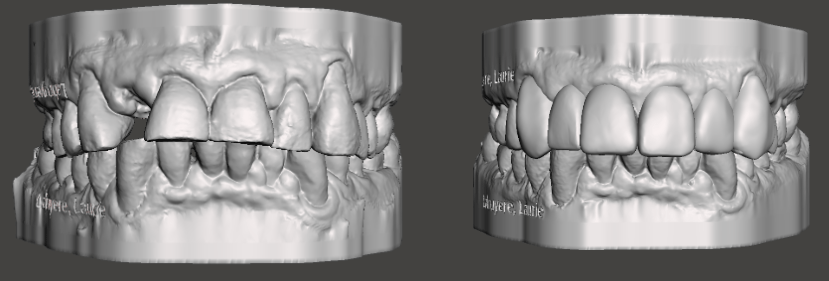

Worn or mal (bad) occlusion

Centrals, laterals and canine all worn flat by bruxism. The anterior teeth are either flat and in more severe cases presents with a an inverted smile line